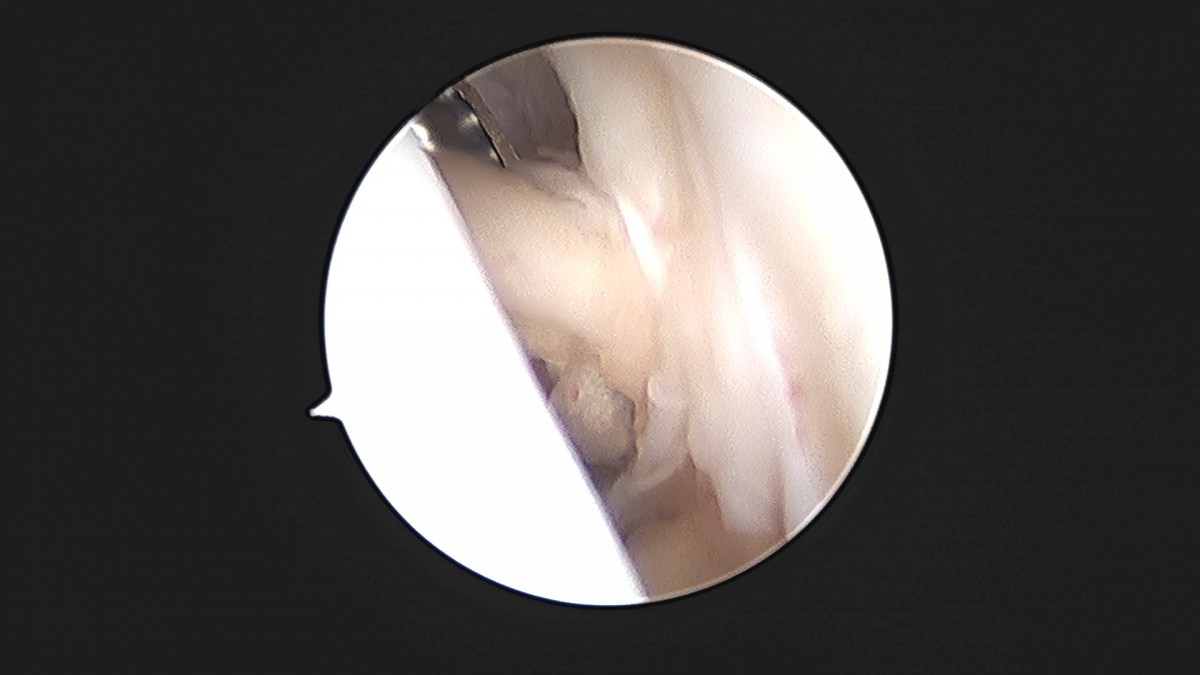

이재상원장님 발목 인대 봉합술 이주O 환자

dae765e4d9ac96aee867c9d6292d8784_1758007208_9216.jpg